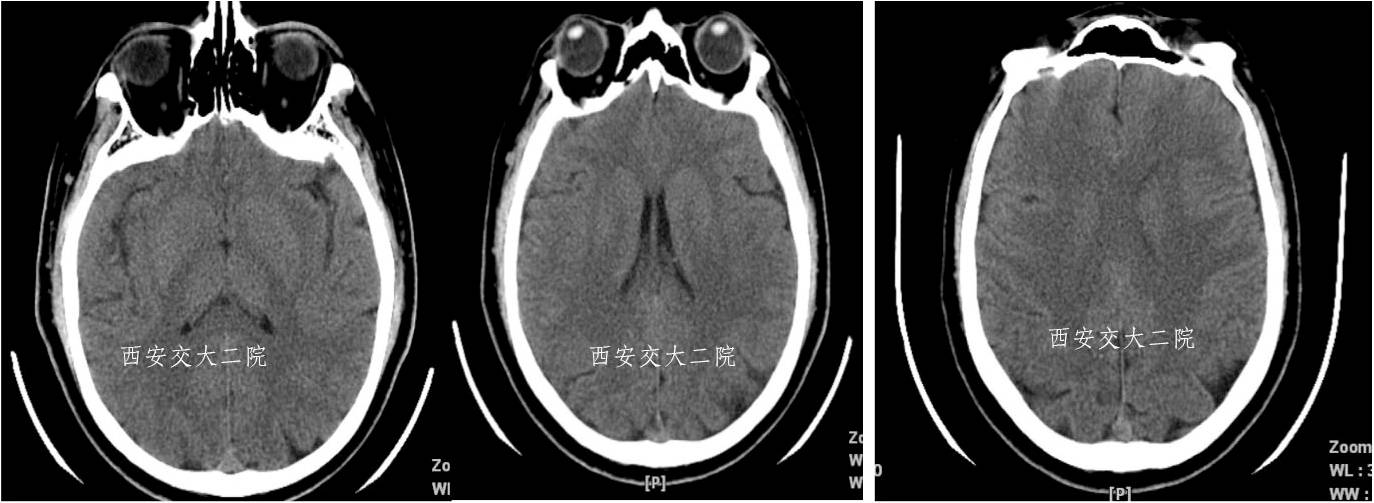

术前CT(病后1h)

术后即刻病情及脑CT

术后24小时脑CT